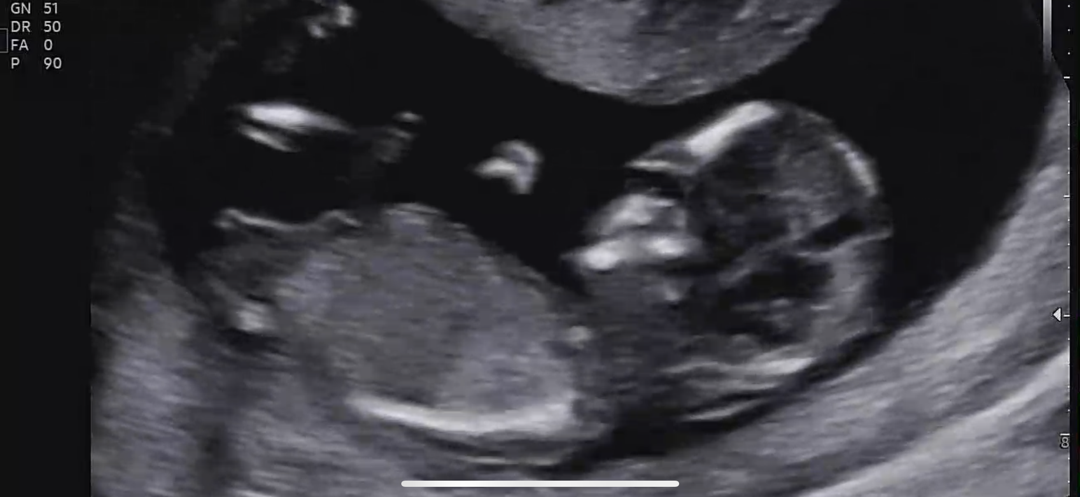

12주 각도법 문의드려요❤️

12주 각도법 봐주실분 계실까요?? 🙂